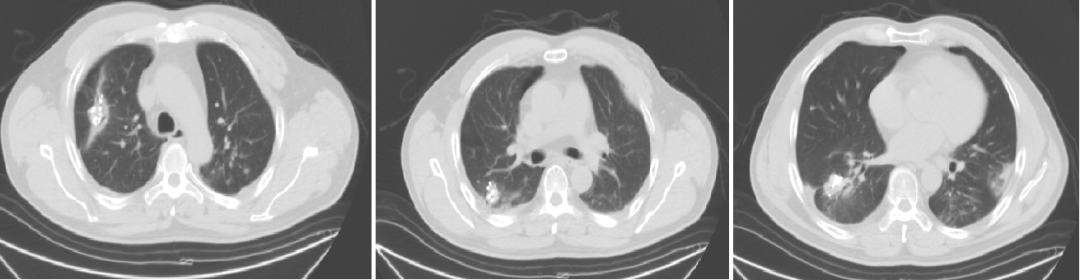

2020-1-7强化CT(我院)

入院诊断:直肠(上段)中分化腺癌;cT0N0M1,IV期;双肺转移;MSS型,RAS/BRAF基因野生型;ERBB2基因扩增型。